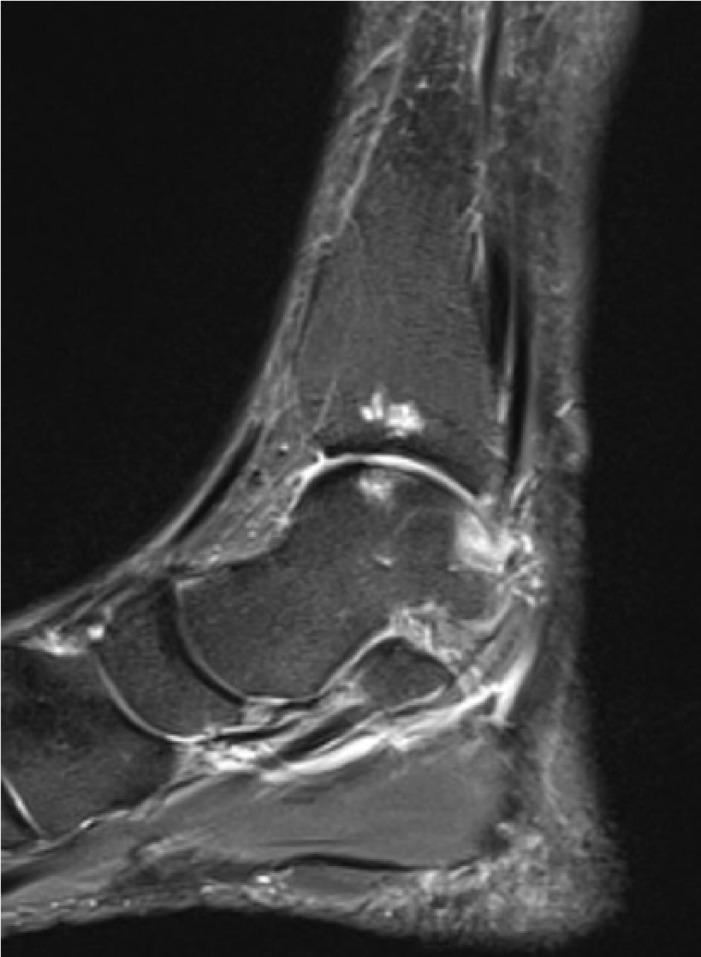

We reviewed and analysed this patient's records containing the sport-specific anamnesis, pre-existing condition, anamnesis of medications and therapy. The three injuries were magnetic resonance imaging-proven. Furthermore, the tendon's condition was examined histologically in the context of the operative treatment through lace technique of the Achilles tendon and transfer of the peroneus brevis to the peroneus longus. We also researched the literature for bilateral ruptures of the peroneal tendons.

我们回顾并分析了该患者的记录,包括运动专项病史、既往病史、用药史和治疗情况。这三处损伤均经磁共振成像证实。此外,在通过跟腱编织技术和将腓骨短肌转移至腓骨长肌进行手术治疗的过程中,对肌腱状况进行了组织学检查。我们还在文献中搜索了腓骨肌腱双侧断裂的病例。